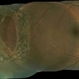

- giant retinal tear, barrier laser, fresh laser burns

- Maria Pei, Bellevue Hospital, New York University, NY

Topcon TRC 501x - Description

- Fundus Photograph of the right eye of a 51-year-old taxi driver with a newly lasered giant retinal tear. He had a history of a retinal detachment from a giant retinal tear in his left eye.